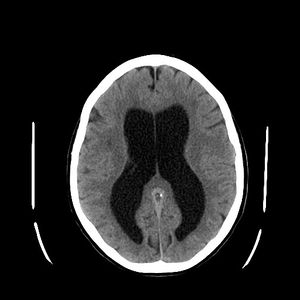

| استسقاء المخ كما يظهر في الأشعة المقطعية على المخ. المناطق السوداء في منتصف المخ هي تضخم غير طبيعي ومملوء بالسوائل. | |

- استسقاء الرأس ex vacuo يشير إلى التضخم في نظام البطينات والمنطقة تحت العنكبوتية. وهو بالعادة يحدث نتيجة لضمور الدماغ (كما يحدث في حالات الخرف), بعد إصابات الدماغ نتجية اضربات وأيضاً في بعض الأمراض النفسية، مثل الفصام. على العكس من استسقاء الرأس، فإن هذا يحدث نتيجة توسع مناطق تواجد السائل النخاعي تعويضاً لما تم فقدانه من نسيج الدماغ – وليس نتيجة لازدياد ضغط السائل النخاعي.